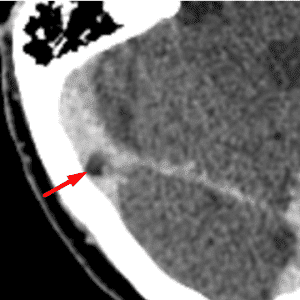

Arachnoid Granulation

Mimicking thrombus